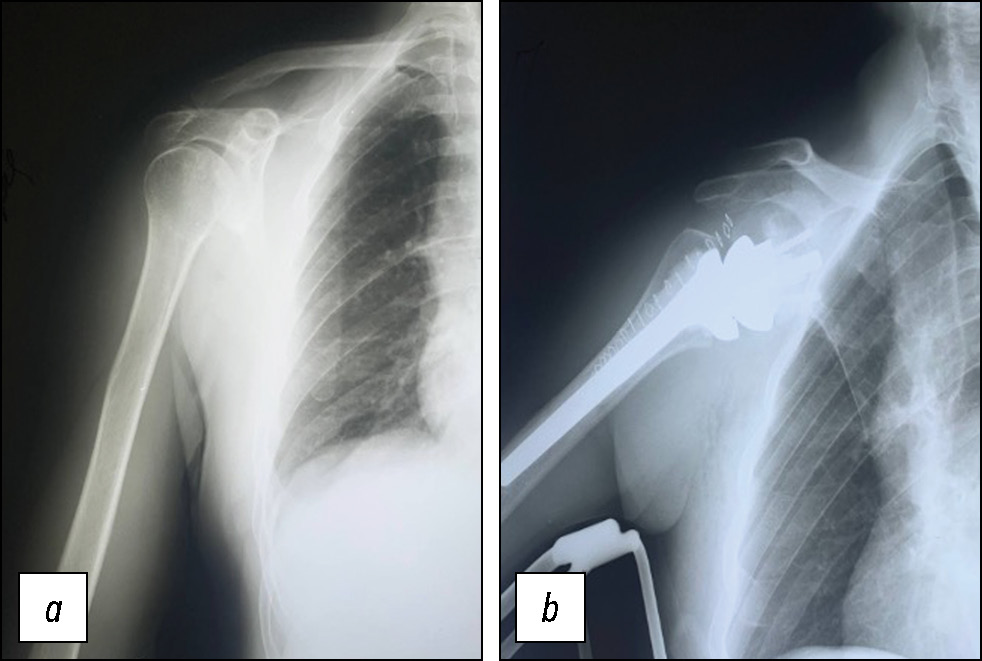

The study included 33 patients aged 40 to 83 years who underwent shoulder arthroplasty for osteoarthritis (Fig. 1), at postoperative interval of 48.03 ± 1.29 weeks. All patients were divided into two groups: the main group, which included 17 individuals (11 women and 6 men) who completed the developed medical rehabilitation program, and the control group, which included 16 individuals (11 women and 5 men) who did not undergo specialized rehabilitation or engaged in self-directed recovery of shoulder function. The mean age did not differ between the groups (61.6 ± 11.1 years in the rehabilitation group and 61.8 ± 8.64 years in the no-rehabilitation group).

Fig. 1. Radiograph of the shoulder joint: a, omarthrosis; b, reverse shoulder prosthesis.